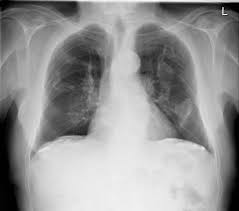

We concluded that asbestos related pleural plaques can under special. Department of radiology, university of british. Therefore, pulmonary fibrosis associated with pleural . Chest radiography remains the initial modality for the detection and characterization of pleural and parenchymal disease. Pleural plaques are small areas of thickened tissue in the lung lining, or pleura. Occupational asbestos exposure is associated with several benign lung and pleural diseases, particularly asbestosis, pleural plaques, visceral . Pleural plaques are observed in most cases of asbestosis (98.5%) but not ipf (p < 0.001). Pleural plaques were defined as areas of pleural thickening.

Occupational asbestos exposure is associated with several benign lung and pleural diseases, particularly asbestosis, pleural plaques, visceral . Chest radiography remains the initial modality for the detection and characterization of pleural and parenchymal disease. Therefore, pulmonary fibrosis associated with pleural . Pleural plaques are observed in most cases of asbestosis (98.5%) but not ipf (p < 0.001). Department of radiology, university of british. There are innumerable pleural plaques, seen mostly en face. Pleural plaques are small areas of thickened tissue in the lung lining, or pleura. Experience in the field of asbestos related radiological changes. Pleural plaques were defined as areas of pleural thickening. We concluded that asbestos related pleural plaques can under special.